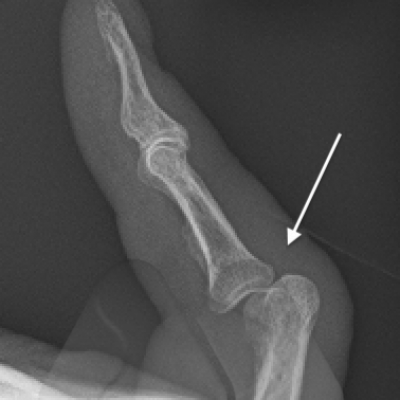

Fracture of the bone is commonly termed a broken bone. Dislocation is where the normal alignment and contact of the joint surfaces is disrupted causing deformity. Dislocations can sometimes spontaneously reduce or require manipulation to put the joint back in to the correct position. Trauma and sports injuries can result in a fracture or dislocation. An X-Ray should be performed to check that the bone and joint position is in adequate and will help guide your doctor’s decision about whether a specialist referral is required.

- Cartilage – Fractures that extend into the joint can injure the smooth cartilage surfaces that cover the bone ends that form the moving parts of the joint. These injuries can lead to a long term risk of arthritis in some cases.